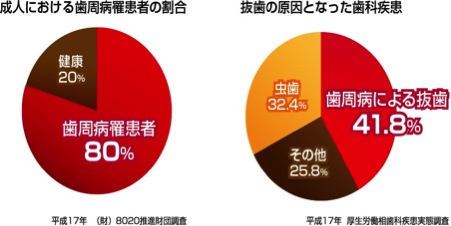

やってますねー。出血するという軽度なものから、もうかなり重症というところを含めて、日本人の「30代の8割が歯周病」という報告が出ています。

日本では30代以上の8割、5人に4人ですよ。かなり高確率のロシアンルーレット状態。

そうなんです。痛くないと歯医者さんに行かないのが日本人。こちらのデータをみて下さい

70歳で歯が何本残っているかを調査したら、日本は8本でしたが予防で有名なスウェーデンは20本、欧米諸国でも15本でした。そもそもどうして歯が無くなるか知っていますか?

へー、意外。抜歯の原因って虫歯より、歯周病の方が多いんだ。